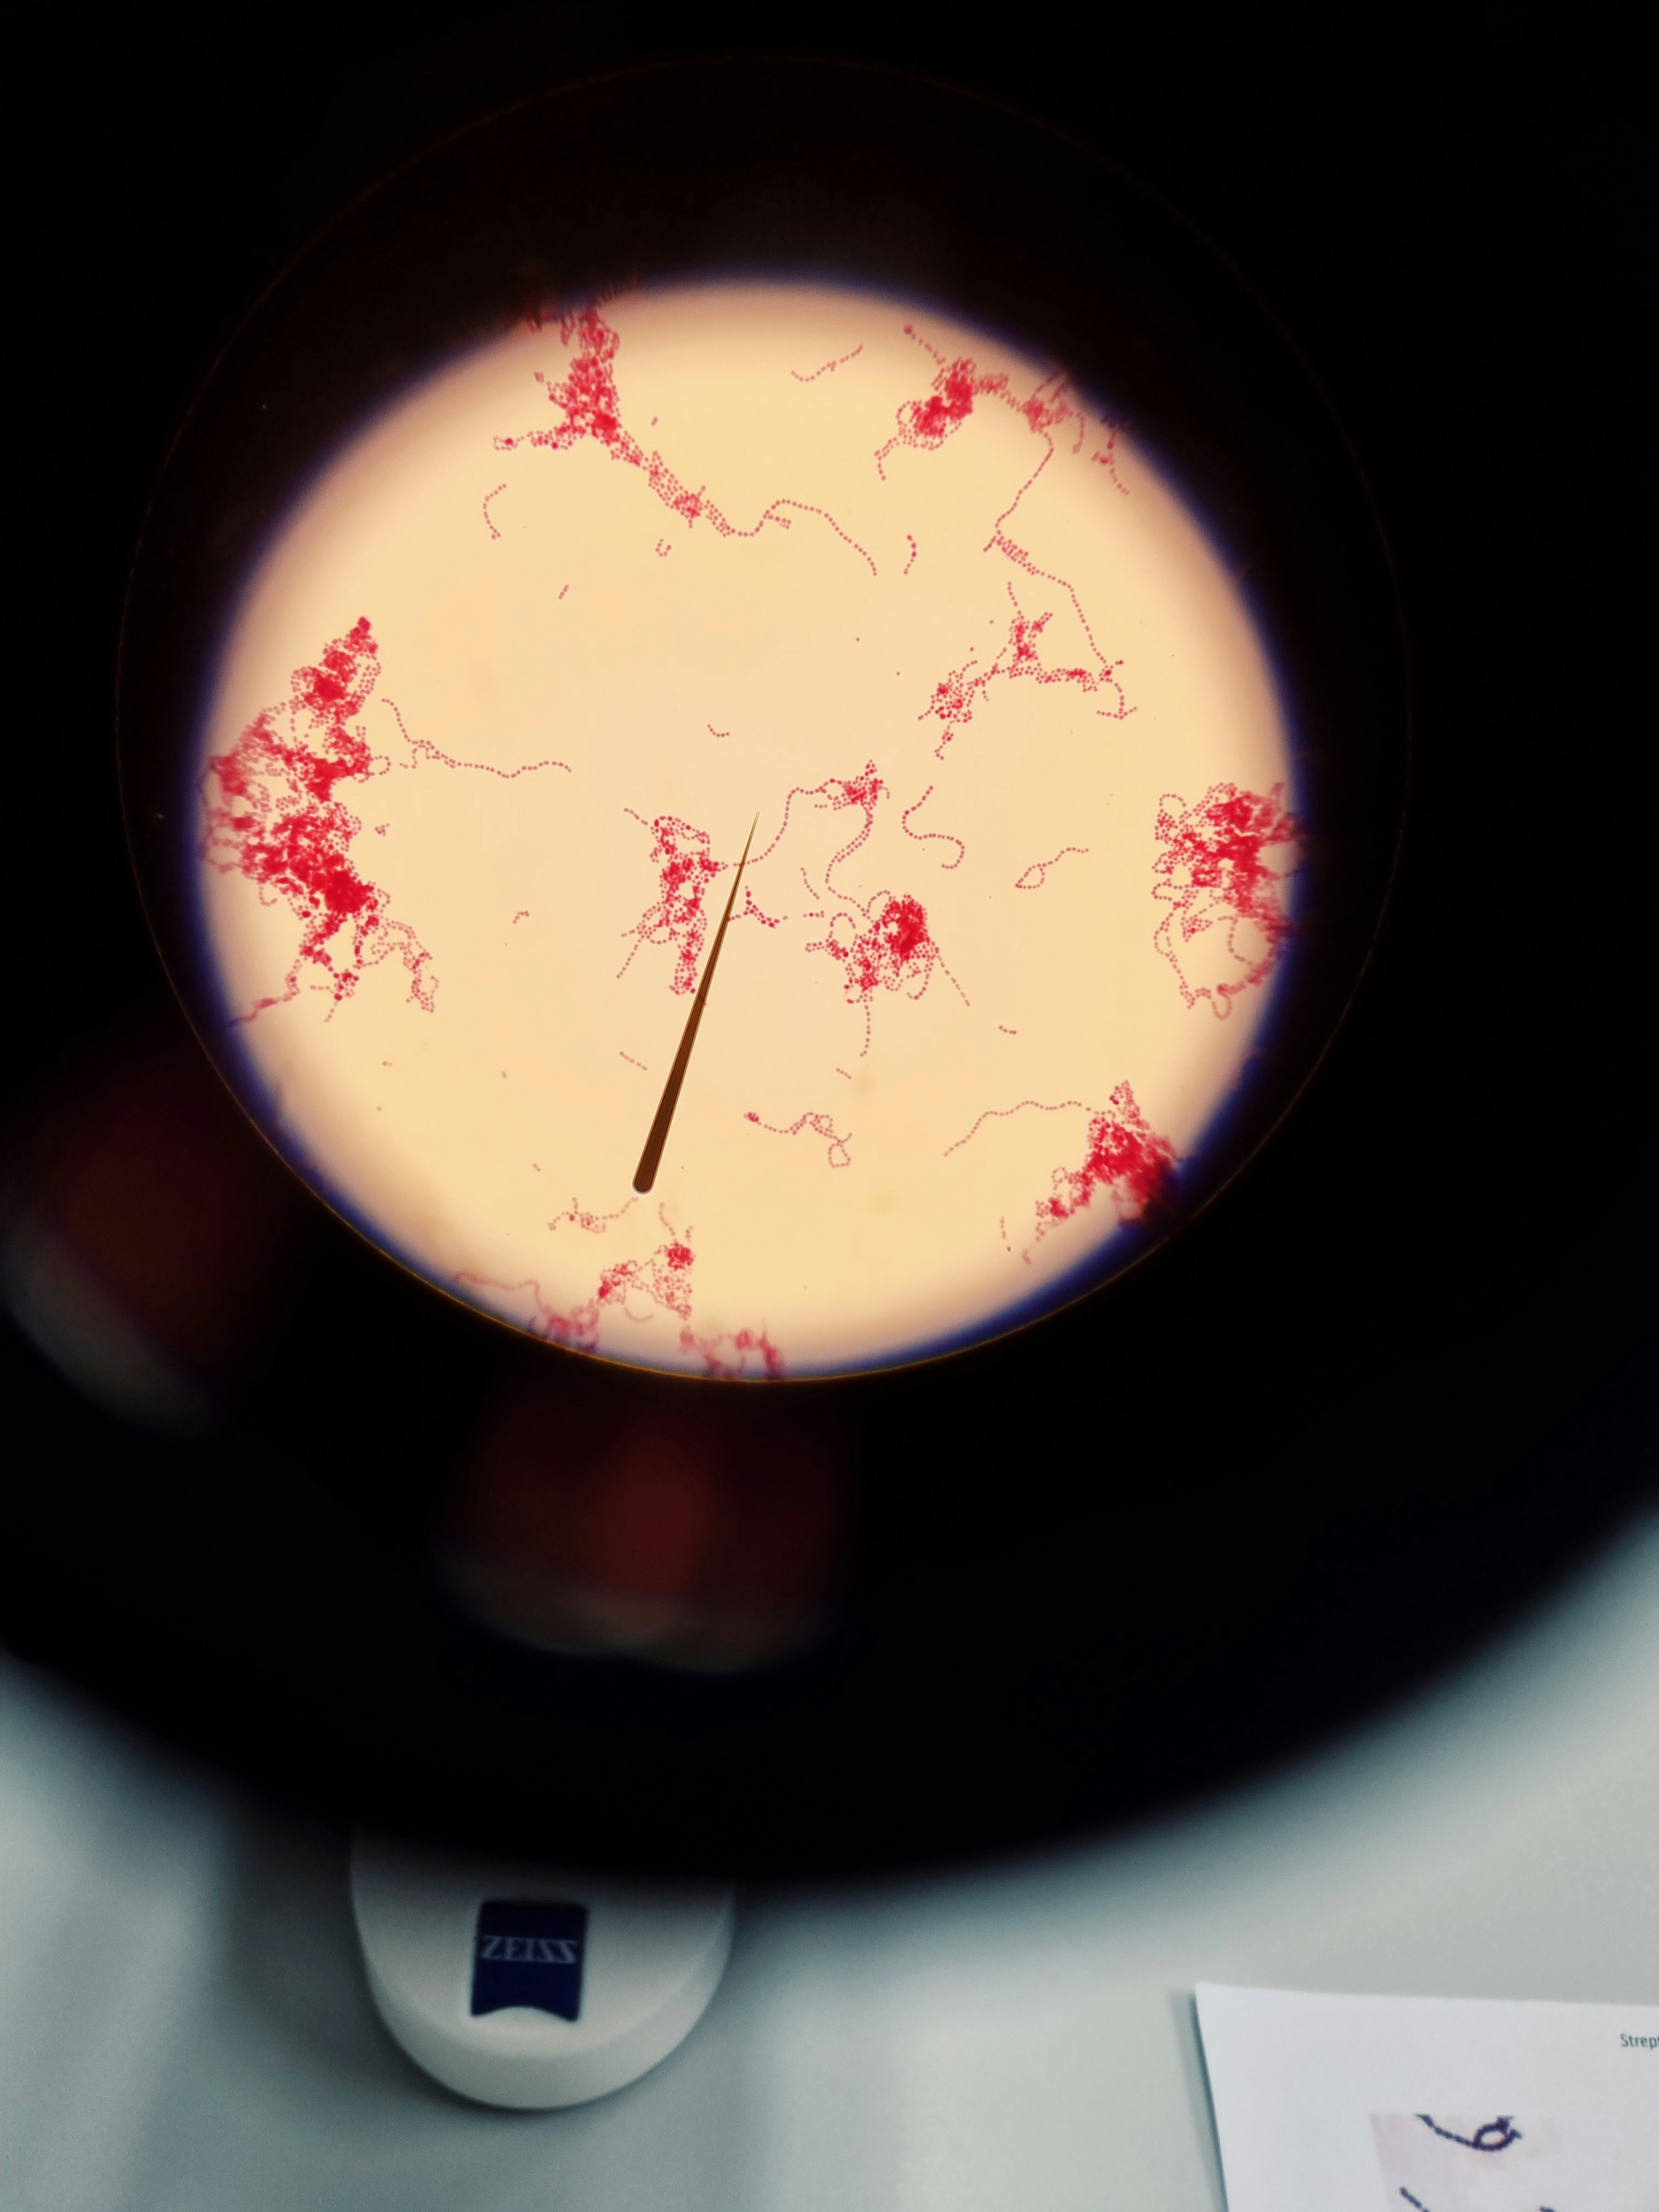

Kingdom Monera -NCERT-NEET-Bacteria are the sole members of the Kingdom Monera. They are the most abundant micro-organisms. Bacteria occur almost everywhere. Hundreds of bacteria are present in a handful of soil. They also live in extreme habitats such as hot springs, deserts, snow and deep oceans where very few other life forms can survive. Many of them live in or on other organisms as parasites

General Characteristics of Monera General Characteristics Kingdom Monera: Bacteria Bacteria are the sole members of…